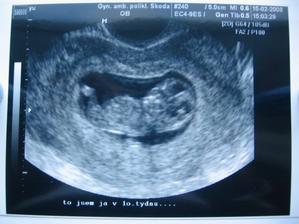

•••••••••• 15.2.2008 ultrazvuk v MB,dle utz 10tt+1, konečně jsme si řekli o naší první fotečku a hlavně jsme dostali těhu průkazku, jsme šťastný jak blechy a pořád ze zubíme a koukáme na fotečku :o)